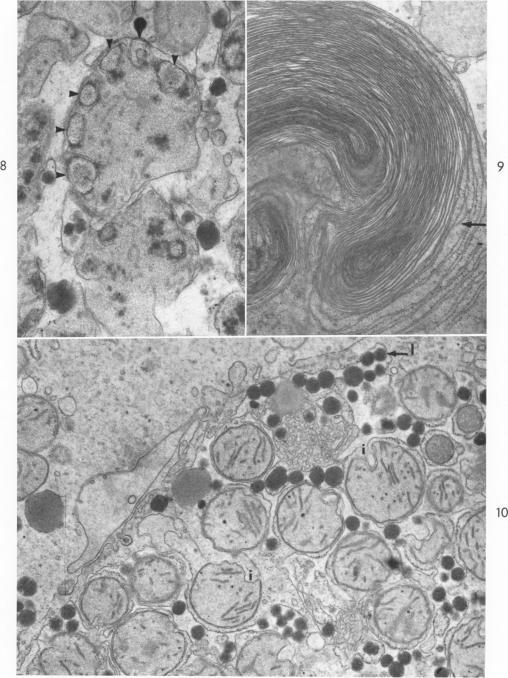

Aflatoxin B1 injury in rat and monkey liver.

Am J Pathol. 1966 Dec;49(6):1023-51.